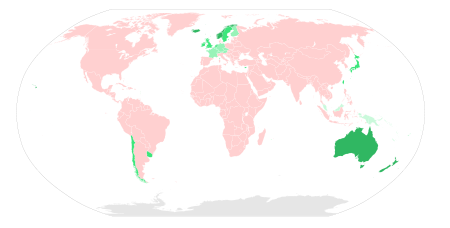

Rabies causes about 55,000 human deaths annually worldwide. 95% of human deaths due to rabies occur in Asia and Africa. Roughly 97% of human rabies cases result from dog bites. In the US, animal control and vaccination programs have effectively eliminated domestic dogs as reservoirs of rabies. In several countries, including Australia and Japan, rabies carried by terrestrial animals has been eliminated entirely. While classical rabies has been eradicated in the United Kingdom, bats infected with a related virus have been found in the country on rare occasions.

The rabies virus survives in widespread, varied, rural fauna reservoirs. It is present in the animal populations of almost every country in the world, except in Australia and New Zealand. Australian bat lyssavirus (ABLV) discovered in 1996 is similar to rabies, and is believed to be prevalent in native bat populations. In some countries, such as those in western Europe and Oceania, rabies is considered to be prevalent among bat populations only.

In Asia, parts of the Americas, and large parts of Africa, dogs remain the principal host. Mandatory vaccination of animals is less effective in rural areas. Especially in developing countries, pets may not be privately kept and their destruction may be unacceptable. Oral vaccines can be safely distributed in baits, a practice that has successfully reduced rabies in rural areas of Canada, France, and the United States. In Montréal, Canada, baits are successfully used on raccoons in the Mont-Royal Park area. Vaccination campaigns may be expensive, and cost-benefit analysis suggests baits may be a cost-effective method of control.

An estimated 55,000 human deaths occur annually from rabies worldwide, with about 31,000 in Asia and 24,000 in Africa. India has the highest rate of human rabies in the world, primarily because of stray dogs, whose number has greatly increased since a 2001 law forbade the killing of dogs. 20,000 people are estimated to die every year from rabies in India — more than a third of the global toll. As of 2007, Vietnam had the second-highest rate, followed by Thailand; in these countries, the virus is primarily transmitted through canines (feral dogs and other wild canine species). Another source of rabies in Asia is the pet boom. In 2006 China introduced the " one-dog policy" in Beijing to control the problem.

Rabies is common among wild animals in the US. Bats, raccoons, skunks and foxes account for almost all reported cases (98% in 2009). Rabid bats are found in all 48 contiguous states. Other reservoirs are more limited geographically; for example, the raccoon rabies virus variant is only found in a relatively narrow band along the East Coast. Due to a high public awareness of the virus, efforts at vaccination of domestic animals and curtailment of feral populations, and availability of postexposure prophylaxis, incidents of rabies in humans are very rare. A total of 49 cases of the disease were reported in the country in 1995-2011; of these, 11 are thought to have been acquired abroad. Almost all domestically acquired cases are attributed to bat bites.